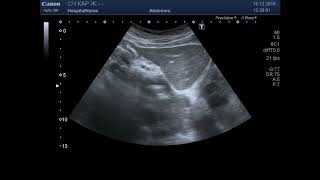

Лечение больной раком шейки матки IIb стадии. Клинический случай: